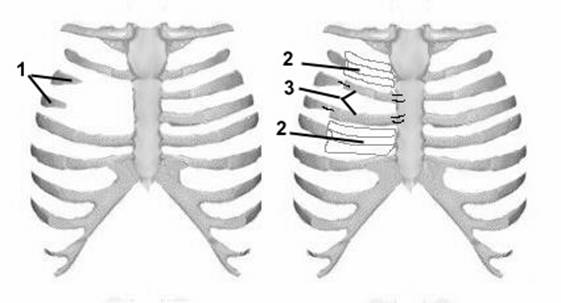

Медицина и диагностика: Аномалии ребер на рентгене